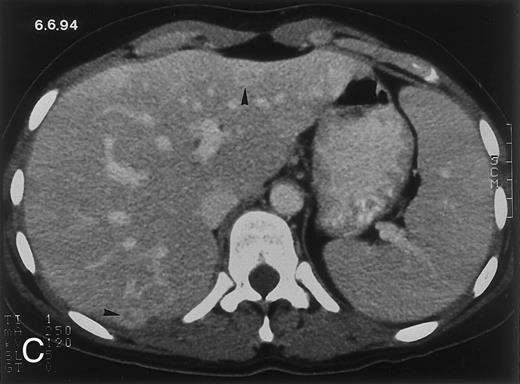

Radiologic evolution in patient B. (A) Postcontrast abdominal CT scan on February 10, 1994 shows multiple small hypodense areas in all segments of the liver suggestive of hepatic candidiasis. Twenty-four days previously, the patient had recovered from severe neutropenia after the second cycle of chemotherapy for ALL. (B) On May 4, 16 days after the neutrophil count had dropped below 500/μL in the third chemotherapy cycle, there is clear improvement of the radiologic findings, with only a few hypodense areas in the liver.

(C) On June 6, 31 days after normalization of neutrophils, CT again shows multiple lesions in the liver (arrowheads) with a different presentation: the small lesions show strong peripheral enhancement. (D) On September 2, 129 days after neutrophil recovery, all hepatic lesions have completely resolved.

Evolution of fungal lesions on CT scans during and after neutropenia is summarized in Table 2. Figure 1 (patient A) and Fig 2 (patient B) serve to illustrate Table 2.

In three patients, multiple round lesions were seen on postcontrast CT scans of the abdomen in the liver and the spleen, while in two cases, lesions could only be seen in the liver (Table 2). Following the diagnosis of disseminated candidiasis, these lesions decreased in size and visibility during subsequent neutropenia in three patients (compare Fig 2A and B) and disappeared completely in two patients (compare Fig 1A and B). The numbers of days of severe neutropenia (neutrophils <500/μL) at the time the CT scan was performed are listed in Table 2. After recovery from neutropenia and despite continued antifungal therapy, the size and visibility of the lesions increased again (Fig 1C). Similarly, the number of days since recovery from severe neutropenia (neutrophils >500/μL) are listed in Table 2. In two of three patients treated with another cycle of myeloablative chemotherapy, this waxing and waning pattern of radiologic lesions could be seen again (Fig 1D and E). In all patients, lesions eventually disappeared (Figs 1F and 2D) after prolonged antifungal therapy.